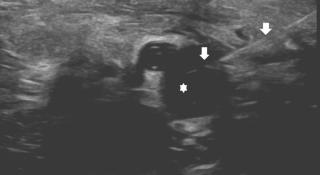

Echogeleide percutane punctie van een arthrosynoviale cyste (asterisk) aan de binnenenkel, verantwoordelijk voor een tarsaal tunnel syndroom

Echogeleide percutane punctie van een arthrosynoviale cyste (asterisk) aan de binnenenkel, verantwoordelijk voor een tarsaal tunnel syndroom. De naald is aangeduid met pijlen.